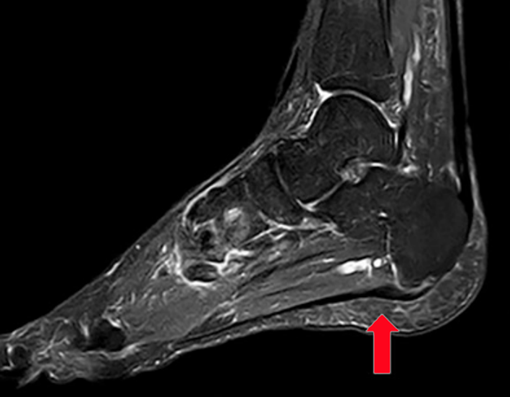

▶核磁共振: 可清楚地显示跖腱膜增厚及周围组织的炎性改变。

跖腱膜在跟骨结节处可见明显增厚(红色箭头)